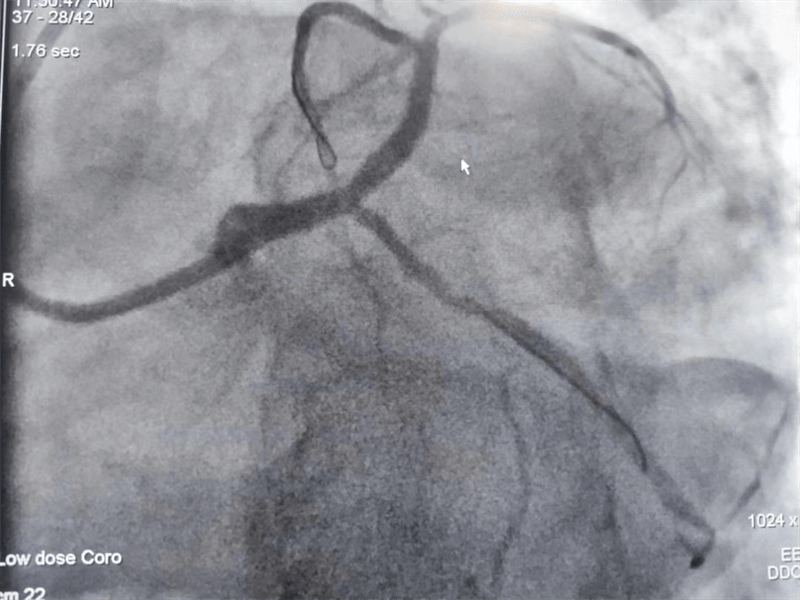

63歲的張大伯因嚴(yán)重心絞痛住院,心電圖可見(jiàn)明顯明顯心肌缺血。主治醫(yī)師黃永濤向患者講明病情后,征得患者和家屬同意,行冠脈造影檢查。真是不做不知道,一做嚇一跳。

冠脈造影結(jié)果提示:左主干末端及前降支開(kāi)口處99%狹窄,回旋支開(kāi)口處80-90%狹窄,中段支架內(nèi)100%閉塞??吹皆煊敖Y(jié)果時(shí),在場(chǎng)醫(yī)護(hù)人員無(wú)不驚出一身冷汗:左主干病變“細(xì)”如發(fā)絲——生死一線牽!患者拒絕搭橋手術(shù),所以選擇介入處理該病變。

患者在冠脈造影檢查術(shù)中,感到胸悶、胸痛發(fā)作,血壓下降、心率減慢,我們立即對(duì)左主干狹窄段進(jìn)行球囊擴(kuò)張后癥狀好轉(zhuǎn),生命體征逐漸平穩(wěn)。